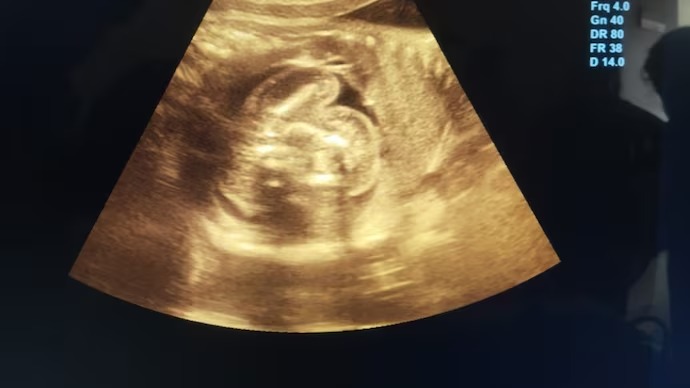

ಅತ್ಯಂತ ಅಪರೂಪದ ವೈದ್ಯಕೀಯ ವಿದ್ಯಮಾನದಲ್ಲಿ, ಮಹಾರಾಷ್ಟ್ರದ ಬುಲ್ಧಾನಾದಲ್ಲಿ ಹುಟ್ಟಲಿರುವ ಮಗುವಿನ ಹೊಟ್ಟೆಯೊಳಗೊಂದು ಬ್ರೂಣ ಪತ್ತೆಯಾಗಿದೆ.

ಎರಡು ದಿನಗಳ ಹಿಂದೆ 32 ವರ್ಷದ ಮಹಿಳೆಯೊಬ್ಬರು ‘ಸೋನೋಗ್ರಫಿ’ಗೆ ಒಳಗಾದಾಗ ಸರ್ಕಾರಿ ಆಸ್ಪತ್ರೆಯಲ್ಲಿ ‘ಭ್ರೂಣದಲ್ಲಿ ಭ್ರೂಣ’ ಪ್ರಕರಣ ಪತ್ತೆಯಾಗಿದೆ. ಈ ಅಪರೂಪದ ಜನ್ಮಜಾತ ಅಸಂಗತತೆಯನ್ನು ವಿಶ್ವಾದ್ಯಂತ ಸುಮಾರು 200 ಪ್ರಕರಣಗಳಲ್ಲಿ ಮಾತ್ರ ದಾಖಲಿಸಲಾಗಿದೆ, ಭಾರತದಲ್ಲಿ ಕೇವಲ 15-20 ಪ್ರಕರಣಗಳು ವರದಿಯಾಗಿವೆ.

“ಆರಂಭದಲ್ಲಿ ನನಗೆ ಆಶ್ಚರ್ಯವಾಯಿತು, ನಂತರ ಚಿತ್ರಗಳನ್ನು ಎಚ್ಚರಿಕೆಯಿಂದ ಮರುಪರಿಶೀಲಿಸಿದೆ” ಎಂದು ಭ್ರೂಣವನ್ನು ಕಂಡುಹಿಡಿದ ಸ್ತ್ರೀರೋಗ ತಜ್ಞ ಡಾ. ಪ್ರಸಾದ್ ಅಗರ್ವಾಲ್ ಹೇಳಿದರು.

“ಅದು ಬೆಳವಣಿಗೆಯಾಗುತ್ತಿರಲಿಲ್ಲ, ಇದು ನಿಜಕ್ಕೂ ಭ್ರೂಣದದೊಳಗೊಂದು ಭ್ರೂಣದ ಪ್ರಕರಣವಾಗಿತ್ತು” ಎಂದು ಅವರು ಹೇಳಿದರು.

ಮಹಿಳೆ ತನ್ನ ಒಂಬತ್ತನೇ ತಿಂಗಳ ಗರ್ಭಧಾರಣೆಯಲ್ಲಿದ್ದಳು, ಈ ಅಸಂಗತತೆಯು ಅತ್ಯಂತ ಅಪರೂಪ ಮತ್ತು ಅನಿರೀಕ್ಷಿತತೆಯಿಂದಾಗಿ ಹಿಂದಿನ ಸ್ಕ್ಯಾನ್ಗಳಲ್ಲಿ ಪತ್ತೆಯಾಗಲಿಲ್ಲ. “ಹಿಂದಿನ ಸೋನೋಗ್ರಫಿಯಲ್ಲಿ ಇದನ್ನು ಪತ್ತೆಯಾಗಿರಲಿಲ್ಲ. ಏಕೆಂದರೆ, ಇದು ಬಹಳ ಅಪರೂಪದ ಸ್ಥಿತಿಯಾಗಿದ್ದು, ಅಂತಹ ಸ್ಥಿತಿ ಅಸ್ತಿತ್ವದಲ್ಲಿರಬಹುದು ಎಂದು ಯಾರೂ ಊಹಿಸಲೂ ಸಾಧ್ಯವಿಲ್ಲ. ಆದ್ದರಿಂದ, ನಾನು ಒಂದೆರಡು ವೈದ್ಯರಿಂದ ವಿವರವಾದ ಅಧ್ಯಯನವನ್ನು ಮಾಡಿ ಅದನ್ನು ದೃಢಪಡಿಸಿದೆ” ಎಂದು ಡಾ. ಅಗರ್ವಾಲ್ ಹೇಳಿದರು.